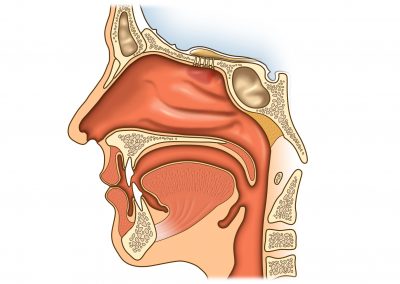

Op. Dr. Atilla Şengör geniz eti muayenesini uygulamalı olarak antatıyor. ...

Çocuklarda sinüzit endoskopik muayene ile teşhis edilebilir. Bunun için günümüzde rontgen benzeri filmlere ihtiyaç duymuyoruz. ...